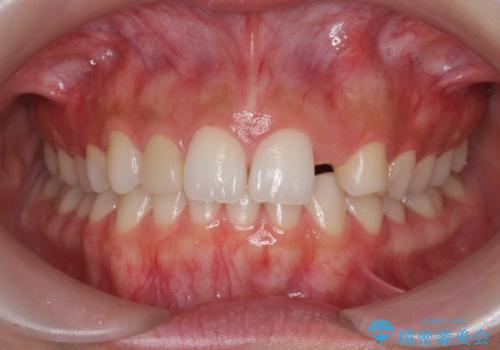

前歯が出っ歯ですきっ歯 抜かずに前歯を見た目良く

- 前歯の並びを主訴に来院。

前歯が出ており、また、左上の側切歯が1本生まれつき少ない状態でした。

今回は左右とも1歯対2歯の関係であるため、それは変えずに前歯を可及的にひっこめて足りない部分をブリッジで補う治療としました。

矯正後の前歯ブリッジについては横浜桜木町歯科の大元院長が担当しています。

奥歯の関係を完全に1級にするには右上の小臼歯の抜歯が必要でしたが、もともと左上の前歯が生まれつき少ないため今回は歯を抜かずに治療しています。